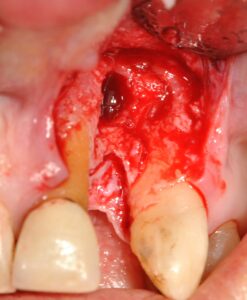

Les techniques de reconstruction osseuse ont évolué dans le sens de la simplification des procédures et des volumes de tissus régénérés.

Nous rappellerons les fondements biologiques de la cicatrisation osseuse, puis une iconographie de cas cliniques permettra de visualiser l’évolution de différentes techniques depuis une vingtaine d’années.